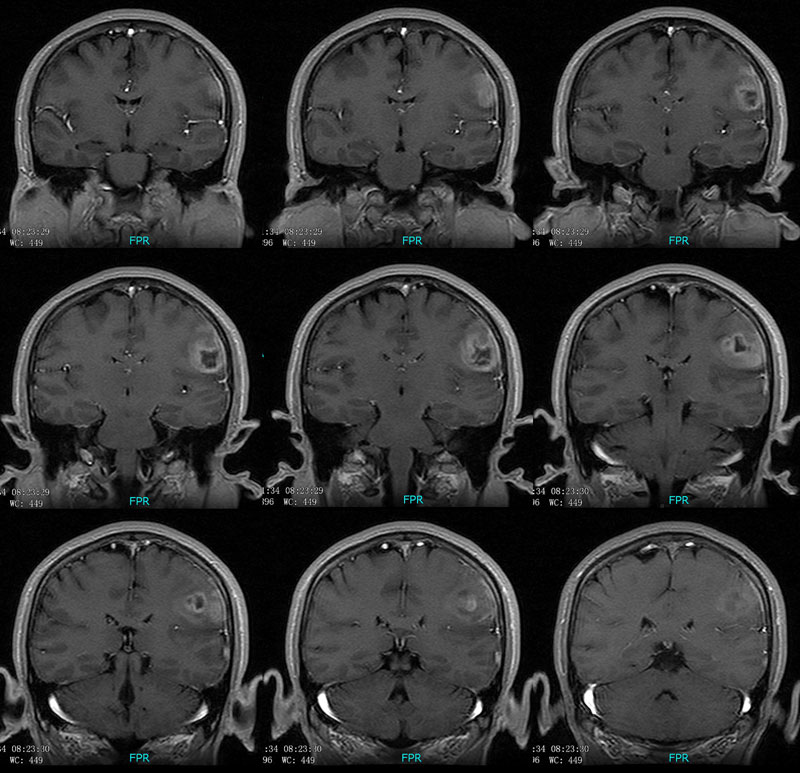

多形性胶质母细胞瘤(额叶)

男性,46岁。

主诉:头晕、头痛2月余,加重10天。

现病史:患者2月余前出现头晕,呈天旋地转,阵发性,伴头痛,多于下午发作,伴右侧口角麻木。近10天患者自觉头晕头痛症状加重。

术后病理多形性胶质母细胞瘤 WHO Ⅳ级。

免疫组化:Vimentin(+),GFAP (+),MGMT个别(+),P53约10%(+),Ki67约20%。

CT平扫呈环形稍高密度,MRI呈长T1长T2,信号稍欠均匀,增强扫呈不规则环形强化,邻近脑膜增厚并明显强化。

左侧顶叶斑片状异常信号,T1低信号,T2高信号,增强后不均匀强化。左侧顶叶多形性胶质母细胞瘤,学习了。